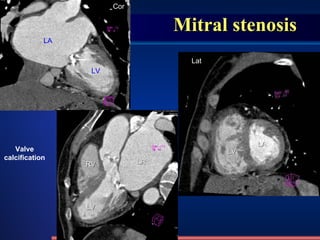

Mitral stenosis LA LV RV LA LV LV LA Valve calcification Lat Cor

Mitral stenosis X-ray  appearance : Cardiac type :“ mitral configuration ” LA & RV enlarged -------  pulmonary artery segment Convexity  LV shrink, Straightening of left heart border ------- Aortic knob shrink valvular calcification Pulmonary venous hypertension, interstitial pulmonary edema Hemosiderin deposited   : 1-2mm nodular shadow /231 LA enlargement PA – right border : Double density of left atrial  enlargement , double PA – left border : left atrial appendage  enlargement Lat & RAO :  esophagus compressed Elevation of left mainstem bronchus   RV enlargement pulmonary artery segment Convexity Lat : contact between the front surface of heart and the sternum (anterior chest wall) >1/3   methods normal abnormities diseases

Mitral stenosis /231 Four arus, diplopia,  Pulmonary venous hypertension LA enlargement PA – right border : double density PA – left border : left atrial appendage enlargement Lat & RAO : esophagus compressed methods normal abnormities diseases